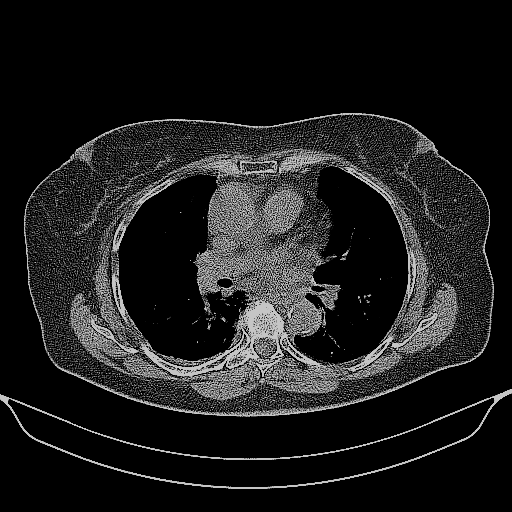

Targeted Slice 70 - Mediastinum Window Analysis (Generated vs Real Venous)

0.655

Mediastinum SSIM

46.3

Mediastinum RMSE

19.4

Mediastinum MAE

Average Mediastinum Window Metrics Across All Slices (161 slices) - Generated vs Real Venous

0.648

Mediastinum SSIM (Avg)

47.9

Mediastinum RMSE (Avg)

20.7

Mediastinum MAE (Avg)

Generated VENOUS CT scan (A→B translation)

Mediastinum window (WL 40, WW 400 β†’ Low βˆ’160, High +240)